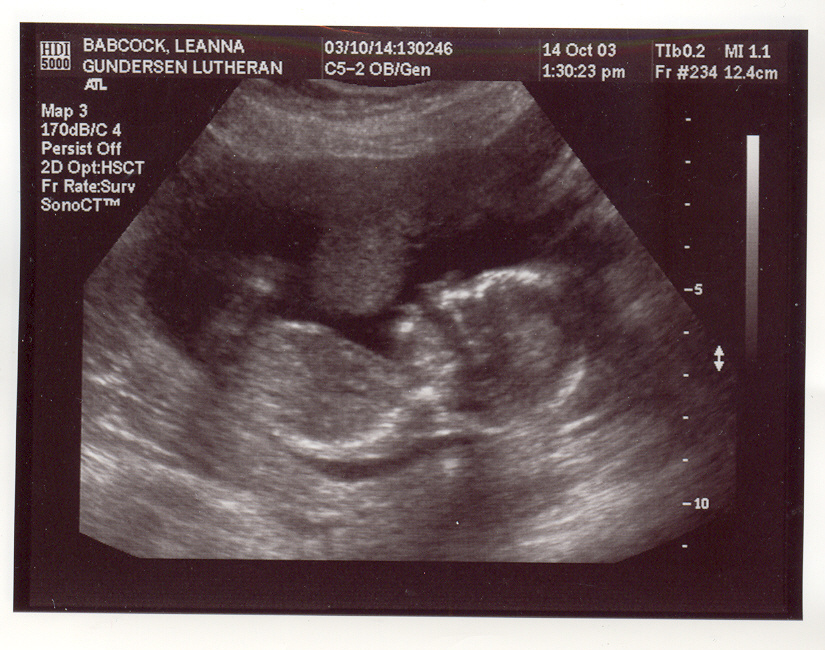

This is my new baby page. I am due at the end of March/start of April, 2004. Here are my first ultrasound pix. They may take a few minutes to load, so be patient. These ultrasound pix were taken Oct. 14th, 2003. We were unable to find out the sex of the baby because it was too early in my pregnancy and also the baby's umbilical cord was between it's legs, and whenever we tried to see what was down there that was blocking our view, and also the baby would put it's hands in the way. I go in for another ultrasound on Nov. 11th. I will post more pix up after then. The baby seems to be healthy at this point and Aidan and I are very excited and preparing for our first child with joy in our hearts! :)